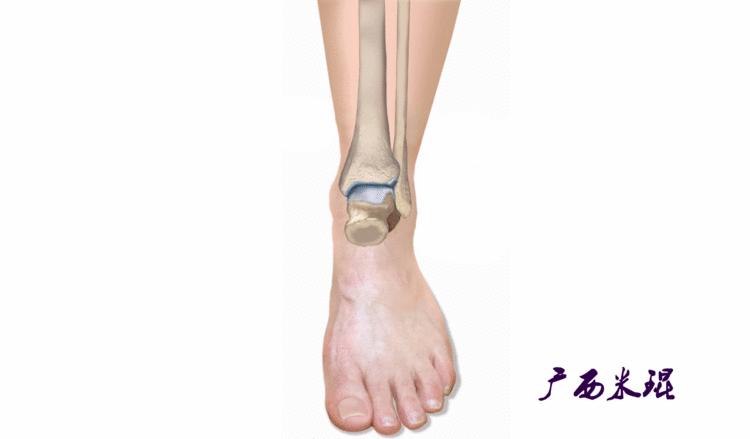

距骨骨软骨损伤(Osteoehondral lesions of the talus, OLT)是指距骨滑车局限性的骨软骨损伤,是累及距骨穹隆关节软骨面和(或)软骨下骨质的损伤,表现为局部关节软骨剥脱,在临床较为常见,损伤后可引起踝关节反复疼痛、肿胀等不适,是踝关节慢性疼痛的主要原因之一。

外伤导致的距骨骨软骨损伤是有一定的规律可循的,前外侧损伤通常是踝关节内翻和背伸*力暴**导致距骨顶的前外侧面撞击腓骨引起的,剪切*力暴**产生切线应力而形成的损伤一般比较浅,接近圆片状。

而后内侧损伤则是由于踝关节内翻、跖屈和外旋*力暴**导致后内侧距骨顶撞击胫骨远端关节面产生相对垂直的*力暴**,从而产生较深的、杯形的损伤。